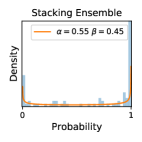

5.1 Distribution of Uncertainty Scores

Distribution of Uncertainty Scores Across Different Severity Levels As explained in Section 3, each uncertainty metric essentially defines an order/ranking among the data points. We conducted an analysis to better understand what data will be assigned high uncertainty under a particular uncertainty metric . Picking out the highest ranked data points (), we calculated the ratio of data points from each SL. Figure 4 summarizes the results as box plots for the Kaggle-DR and the Messidor-2 datasets; additional detailed statistics can be found in Table S.1 in the supplementary materials. From the plot and table, SL1 & SL2 examples account for a higher proportion among the top-ranked uncertain examples across the three ensemble methods. This finding matches our intuition that incipient disease examples (SL1 & SL2) are more likely to be considered uncertain by ensemble methods due to their ambiguity.

Comparing the three ensemble methods in Figure 4, the stacking ensemble method has the highest ratios of SL1 & SL2 data among the high-uncertainty examples it identified under both mean and var. TTA showed slightly better performance than MC-dropout but still falls behind the stacking ensemble method. Considering the fact that SL0 examples accounted for the majority of the dataset, the stacking ensemble method was much more precise (specific) in selecting truly ambiguous data points that were difficult to classify. From Figure 3, we can also see that the stacking ensemble method greatly outperformed the other two methods in finding false negatives under both mean and var uncertainty metrics.

In contrast, the MC-dropout method showed the worst overall performance among the three, as it can be seen from the high ratios of SL0 examples among the uncertain negatives in Figure 4. The histograms in Figure 2 provides another perspective to look into the phenomenon, where a decent proportion of MC-dropout model’s predictions on SL0 inputs entailed low confidence (far from 0 or 1), which from another angle explained why MC-dropout was less specific in terms of lower FNP; many no-DR inputs (i.e. SL0) were erroneously assigned high uncertainty by MC-dropout models.

It is still an open question why the evaluated MC-dropout networks signaled relatively high uncertainty on SL0 & SL3 & SL4 data that are less likely to be ambiguous. We conjecture that much of the “uncertainty” indicated by disagreement among test-time dropout samples actually reflects the stochastic nature of dropout networks rather than the real decision uncertainty associated with the data. It is worth noting that the MC-dropout model we evaluated was not weak per se; they all achieved above Area Under Curve (AUC) scores on test sets. The weakness of individual test-time samples (which explains their low-confidence predictions on SL0 & SL3 & SL4) might have been hidden when they are aggregated into an ensemble—a well-known advantage of ensemble learning. Our results suggested that the uncertainty information given by implicit ensemble methods such as MC-dropout and TTA might not be as reliable as that from explicit ensemble approaches (e.g., stacking ensembles). Similar findings on MC-dropout can be found in some previous papers [1].